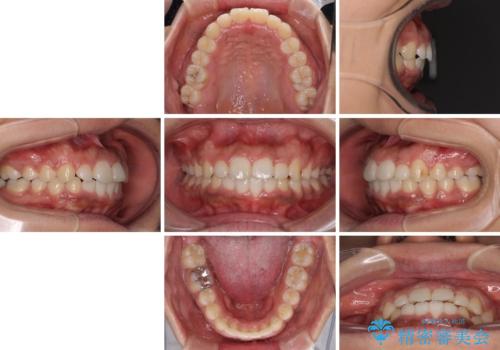

- 上下前歯の叢生を気にして来院された患者様です。

当初はインビザラインにて治療を開始しましたが、自己管理による治療が難しくなり、ワイヤー矯正へ転換して継続しました。

2年ほどインビザライン矯正を続けましたが、終了することができず、ワイヤーへ転換後は1年弱で終えることができました。